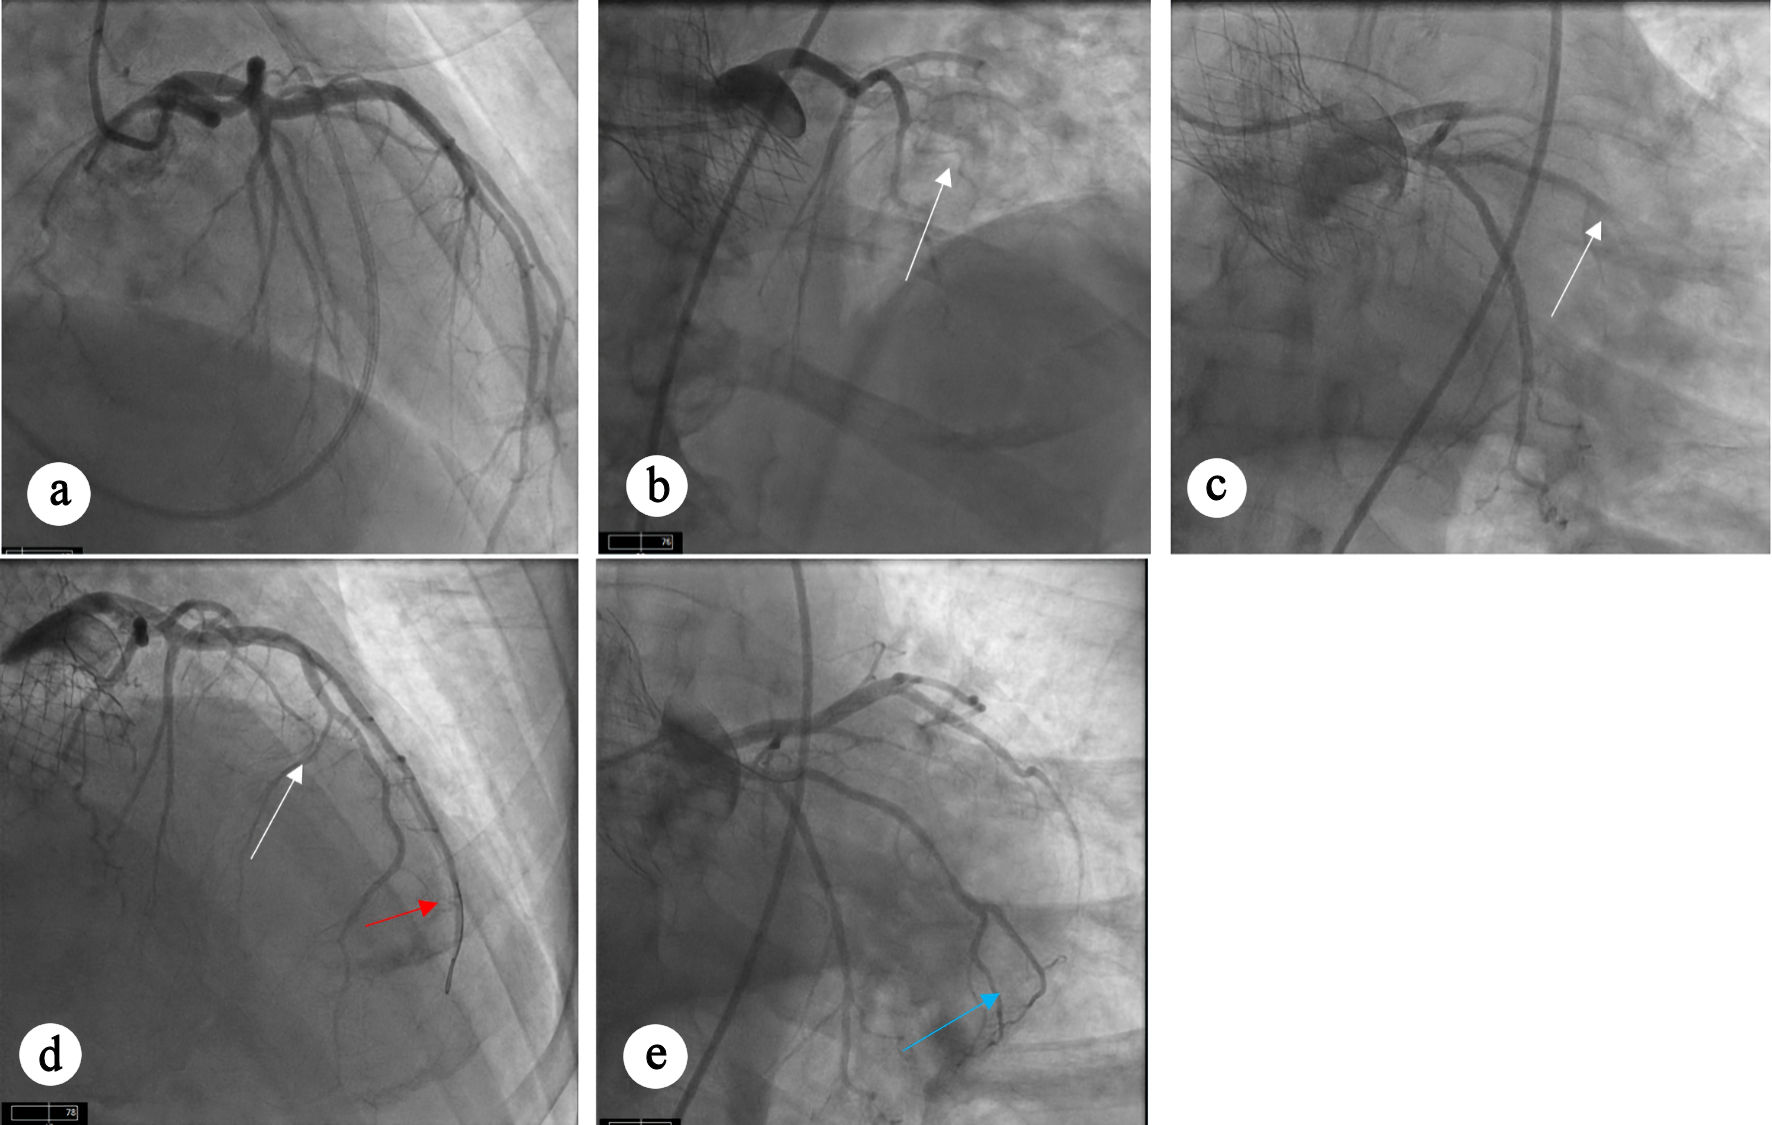

Ten months after TAVR, the patient presented with inferolateral STEMI. Coronary angiography demonstrated abrupt 100% occlusion of the two OM branches (Fig. 2a). Aspiration thrombectomy resulted in restoration of TIMI 3 flow in both OM branches (Fig. 2b). Review of pre-TAVR coronary angiogram confirmed previously patent vessels without any evidence of obstructive CAD (Fig. 2c).

Figure 2. Angiographic views showing occlusion and restoration of flow after intervention. (a) Occlusion of OM branches (white arrows) can be seen. (b) Restoration of flow can be seen in OM branches (white arrow) after aspiration thrombectomy. TAVR valve (red arrow) can also be appreciated. (c) Diagnostic angiogram before TAVR procedure showing patent OM branches. OM: obtuse marginal; TAVR: transcatheter aortic valve replacement.